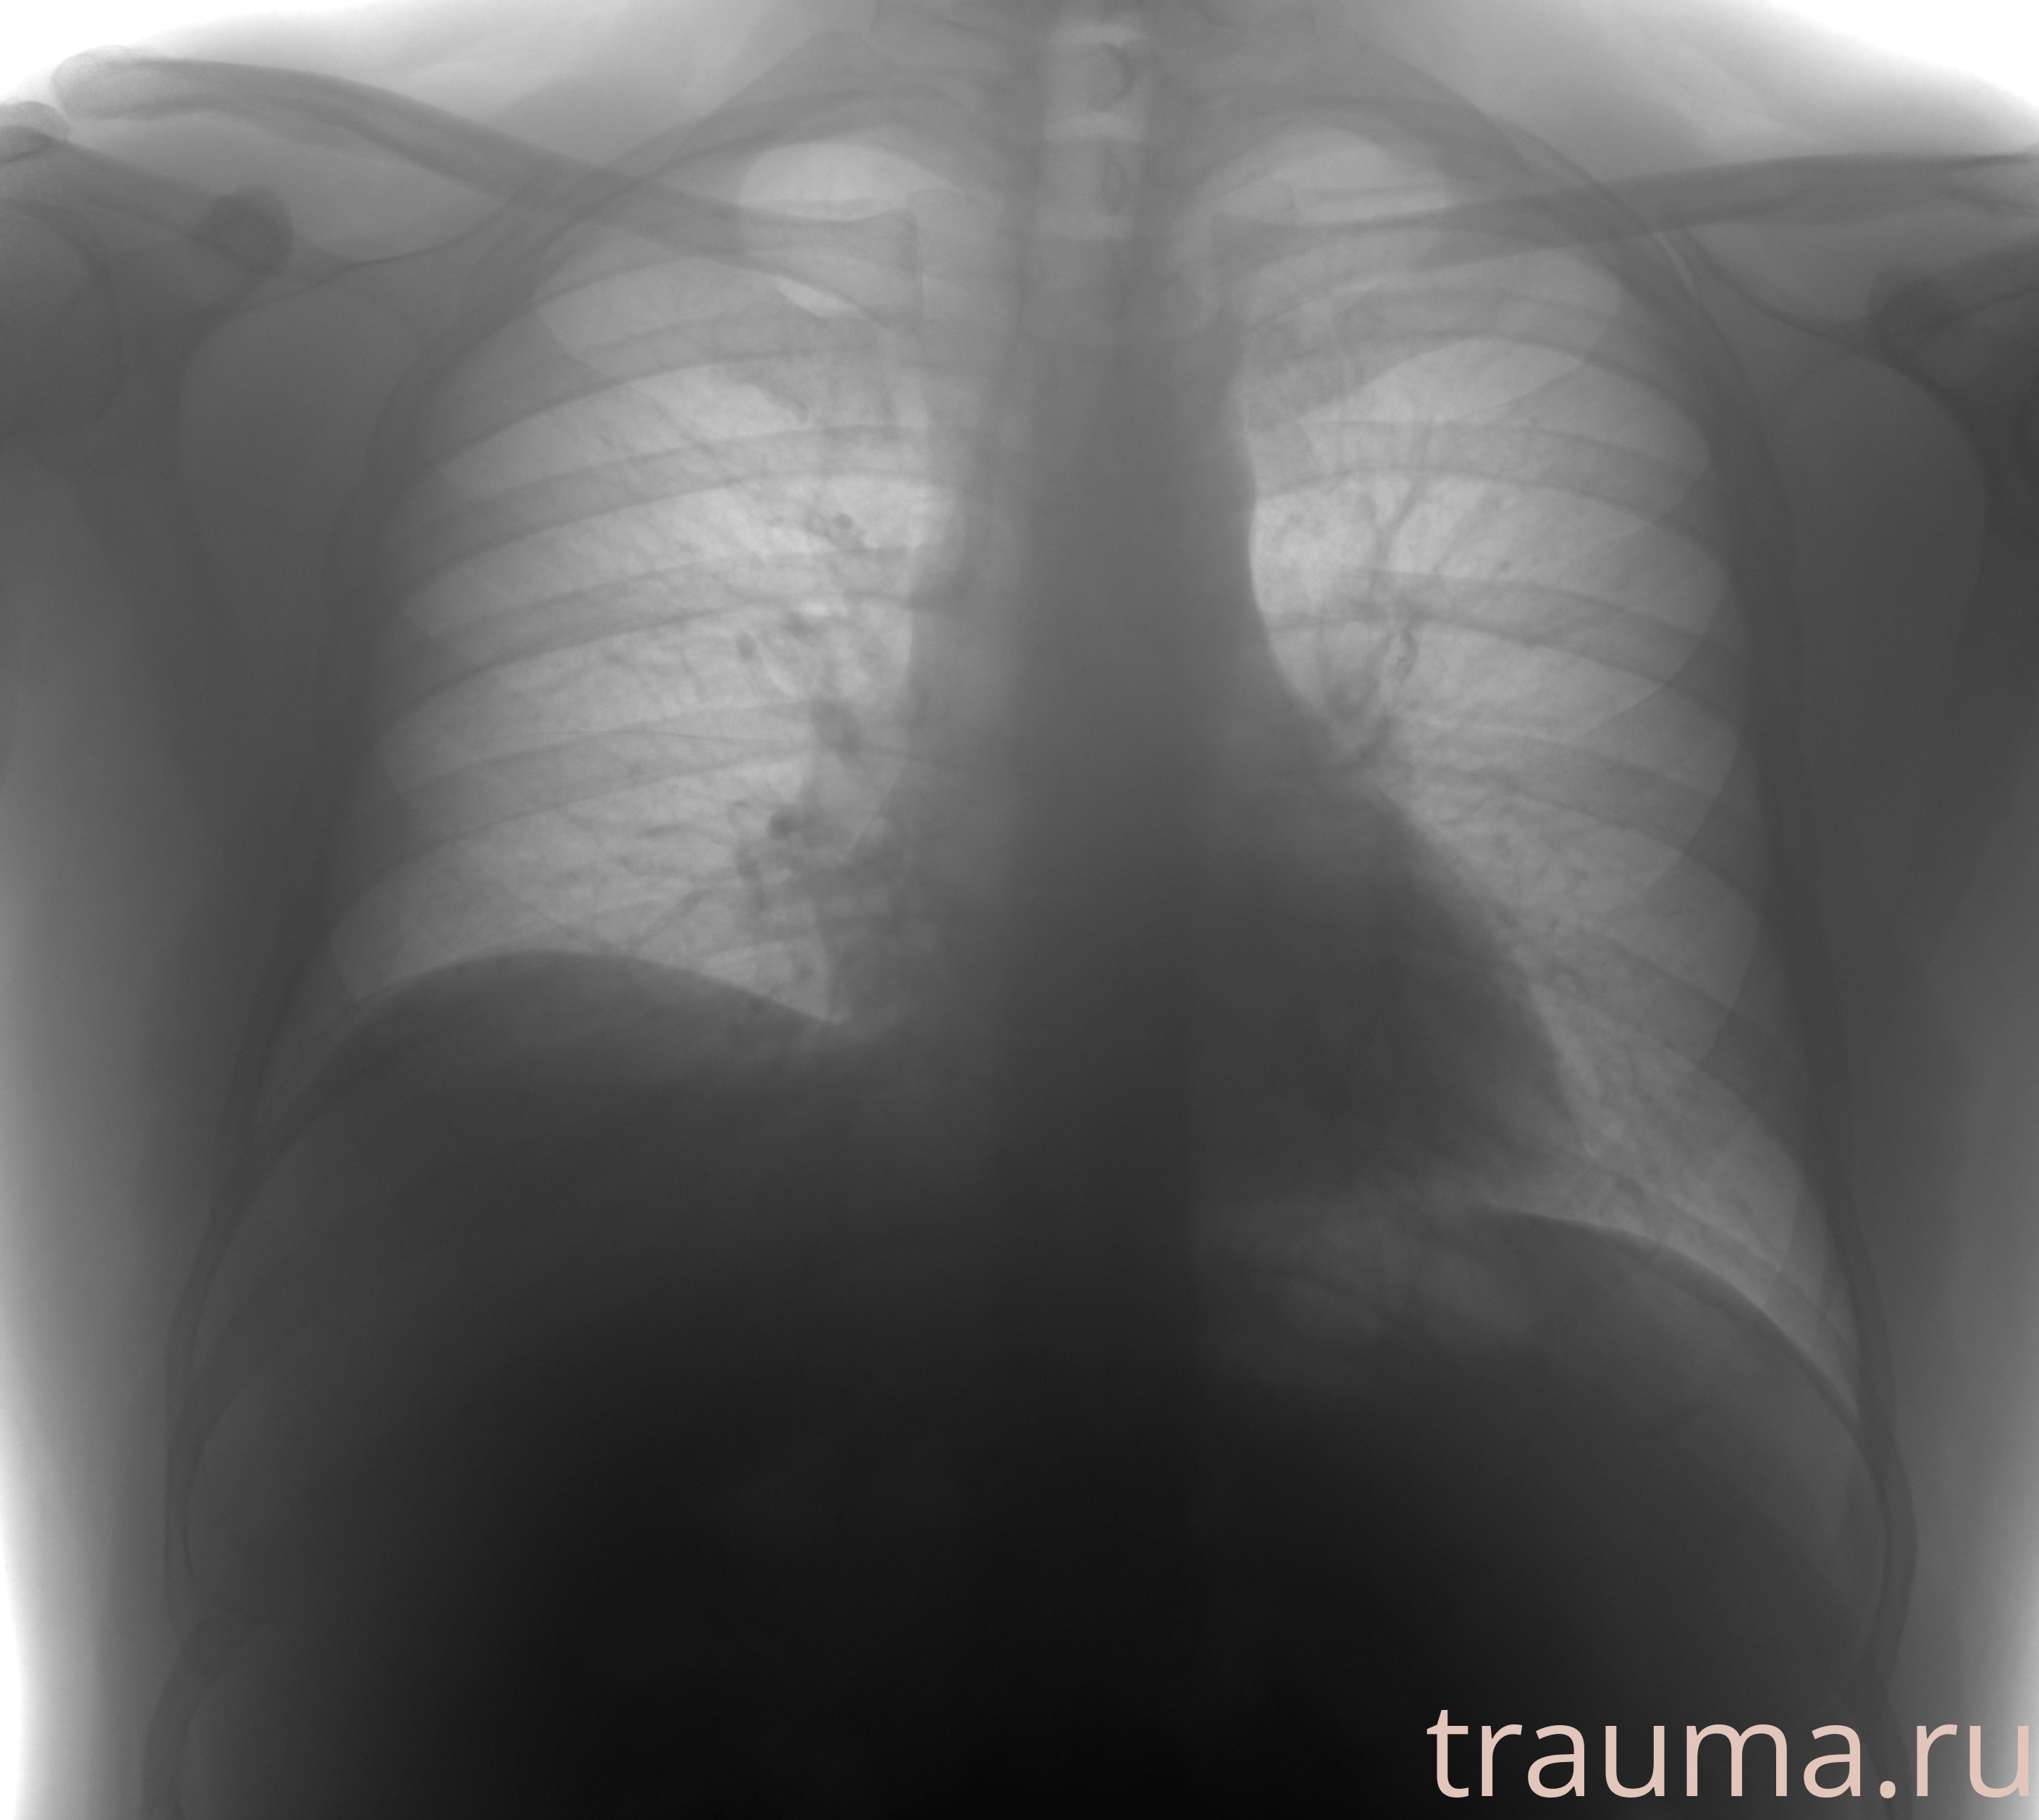

Рентгенограммы

Рентген на дому: по вашему адресу приезжает врач-рентгенолог, травматолог-ортопед с мобильным рентгеновским аппаратом, проводит диагностику травмы или заболевания, делает необходимые рентгенограммы, дает рекомендации по дальнейшему лечению. Получить качественные снимки в домашних условиях возможно благодаря уникальной методике, разработанной МосРентген Центром для института  Склифосовского

при переломе шейки бедра и пневмонии от компании МосРентген Центр - партнера Института имени Склифосовского

Яркость: 1   Контраст: 1   Инвертировать: 0 Увеличение: 1

Перетаскивайте мышь вверх/вниз для контраста, влево/право для яркости. Прокрутка колесом изменяет масштаб. Нажмите Сбросить для возврата к исходному изображению. При увеличении держите мышь в той области, которую хотите рассмотреть.